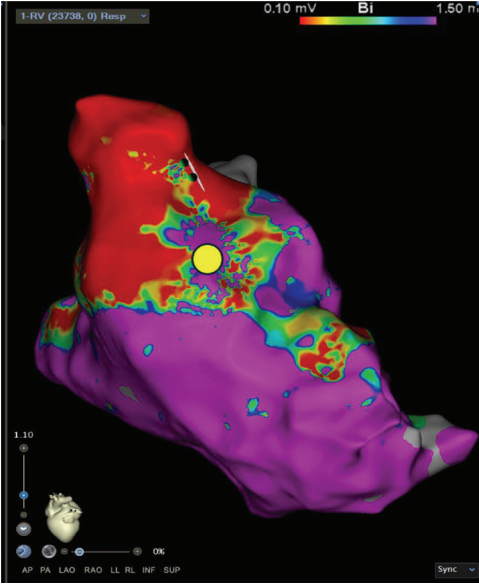

Substrate Mapping

A high-definition map was constructed with an Optrell catheter and RV pacing to better understand the patient’s surgical scar-based substrate before ventricular stimulation (Figure 1). The scar was noted almost exclusively in the RV outflow tract anteriorly stretching across to the tricuspid valve annulus. A small amount of patchy scar was noted in the anterior mid to apical RV as well; however, the septum did not have a significant scar near the predicted VSD Dacron patch. A slowly conducting anatomic isthmus (SCAI) with a conduction velocity of <0.5 m/s was marked (yellow circle, Figure 1). The conduction velocity cutoff of <0.5 m/s has been predictive of arrhythmogenic isthmuses in repaired Tetralogy of Fallot (rTOF).1,2 Preemptive ablation of identified SCAIs is associated with lower rates of VT and ICD implantations in the rTOF population.3 This heterogenous scar area was likely related to the prior RV infundibular muscle resection, surgical PVR 10 years prior, and valve-in-valve TPVR struts just 4 months prior that seemed to play a part in triggering their ventricular arrhythmias.